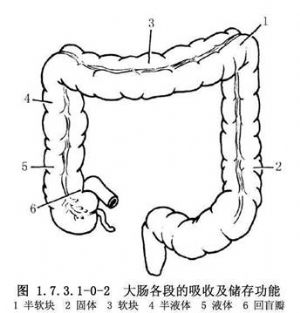

结肠长约1.5m,约为小肠的1/4。结肠外观上有4个特征,易与小肠鉴别:①结肠带:是结肠壁纵肌层集聚而成的3条纵带,自盲肠端至乙状结肠直肠交界处;②结肠袋:因结肠带较短而结肠较长,引起肠壁皱缩成囊状;③脂肪垂(肠脂垂):是结肠的脏层腹膜下脂肪组织集聚而成,沿结肠带分布最多,在近端结肠较扁平,在乙状结肠则多呈带蒂状;④肠腔较大,肠壁较薄(图1.7.3.1-0-1)。结肠分为盲肠、升结肠、横结肠及乙状结肠等。结肠的功能主要是吸收水分和储存粪便(图1.7.3.1-0-2)。吸收作用以右半结肠为主,因其内容物为液体、半液体及软块样,故主要吸收水分、无机盐、气体、少量的糖和其他水溶性物质,但不能吸收蛋白质与脂肪。若右半结肠蠕动降低,则加强吸收能力;横结肠内若有硬的粪块,常导致便秘。左半结肠的内容物为软块、半软块或固体样,故仅能吸收少量的水分、盐和糖。若左半结肠肠蠕动增强,则降低吸收能力,常有腹泻或稀便。结肠黏膜仅能分泌黏液,使黏膜润滑,以利粪便通过。切除结肠后,吸收水分的功能逐渐由回肠所代替,故主要对切除结肠的任何部分,甚至全部,也不致造成永久性代谢障碍。

盲肠位于右髂窝,为升结肠的起始部,与回肠末端相接,在其后下端有盲管状的阑尾。回肠突入盲肠处的黏膜折成唇状为回盲瓣,它具有括约肌的作用,可防止肠内容物反流。盲肠全被腹膜所覆盖,故有一定的活动性。若活动范围过大,可形成移动性盲肠,并可发生扭转,也可进入疝囊中。升结肠是盲肠的延续,上至肝右叶的下方,向左弯成结肠肝曲,其移行于横结肠。升结肠前面及两侧有腹膜覆盖,位置比较固定。但后面以蜂窝组织与腹后壁自右肾和输尿管相隔。结肠肝曲内侧稍上方有十二指肠降部,在右半结肠切除时,切勿损伤十二指肠,特别是有粘连时更应注意。横结肠自结肠肝曲开始,向左在脾下极变成锐角,形成结肠脾曲,向下连接降结肠。横结肠全被腹膜所包裹,并形成横结肠系膜,同时借此系膜连于腹后壁。结肠脾曲的位置较高,上方与胰尾及脾相接近,在结肠切除时须注意对胰、脾的保护。同样,在脾破裂大出血及巨脾切除时,也应随时防止结肠脾曲的损伤。降结肠自结肠脾曲开始,向下至左髂嵴处与乙状结肠相接。降结肠与升结肠大致相同,只在前面和两侧被以腹膜。由于升、降结肠的后面均在腹膜之外,故在腹膜后有血肿存在时,须游离结肠探查其腹膜外部分,以免遗漏造成严重后果。乙状结肠起自左髂嵴,至第3骶椎上缘连于直肠。乙状结肠的系膜比较长,故活动性较大,可能成为肠扭转的诱因之一。